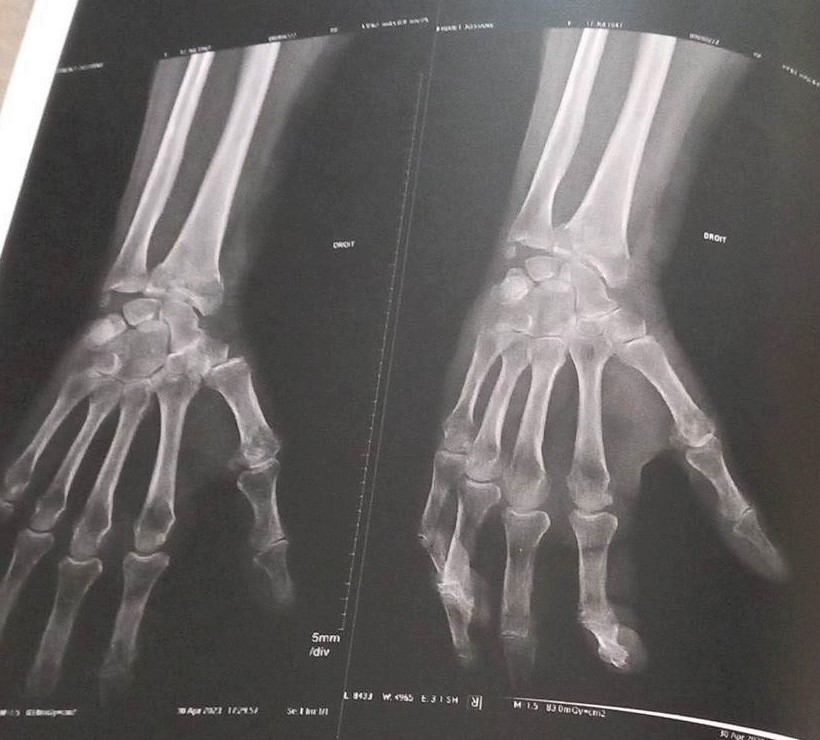

Radio et scanner cérébral à cause de l’hémorragie qui a duré des heures quand même, malgré 2 Coalgan dans la narine jusqu’au lendemain.

Compte rendu : Nez pas cassé, début d’hématome sur la joue; scanner cérébral RAS, mais 2 fractures au poignet.

Bon moi je ne sais pas où ça se trouve, le toubib me montrera j’espère.